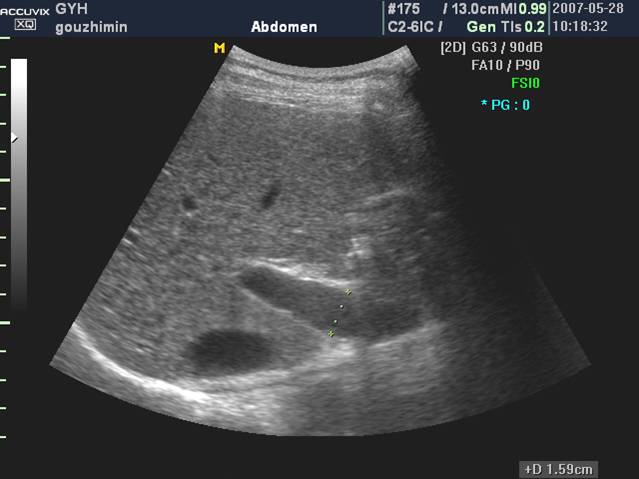

2、肝脏包膜回声增强,表面高低不平,有的呈锯齿状。

3、肝实质回声增强、增粗、不均匀

4、肝静脉变细